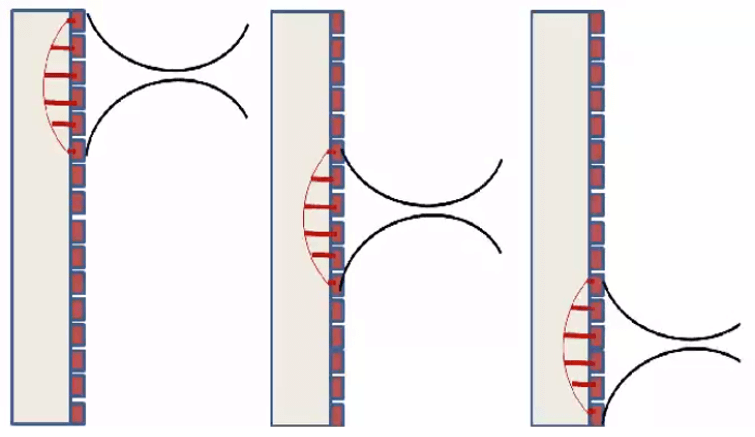

Electronic Beam Focusing

The focusing of some transducers can be adjusted to a specific depth for each transmitted pulse. The transducer is made up of an array of several piezoelectric elements, rather than a single element compared to the fixed focus transducer. As shown in this animation, the elements are arranged in either a straight, or curved line in the linear array.

Focusing is achieved by not applying the electrical pulses to all of the transducer elements simultaneously. The pulse to each element is passed through an electronic delay The outermost elements will be pulsed first, which produces ultrasound that begins to move away from the transducer. The other elements are then pulsed in sequence, working toward the center of the array.

The centermost element will receive the last pulse. The pulses from the individual elements combine in a constructive manner, to create a curved composite pulse, which will converge on a focal point at some specific distance or depth from the transducer.

The focal depth is determined by the time delay between the electrical pulses. Focal Pulses can be changed electronically to give a good image detail at various depths within the body, rather than just one depth compared to the fixed focus transducer. One approach is to create an image by using a sequence of pulses, each one focused on a different depth or zone within the body.

Another approach is a group of piezoelectric elements that work together to produce the focused beam. Each of the transducers is excited with time offsets. The combination of several focal lengths on transmission improves the quality of the image. In return, the frame rate is decreased by a factor equal to the number of selected focal lengths. And last, the image is reconstructed by zone.